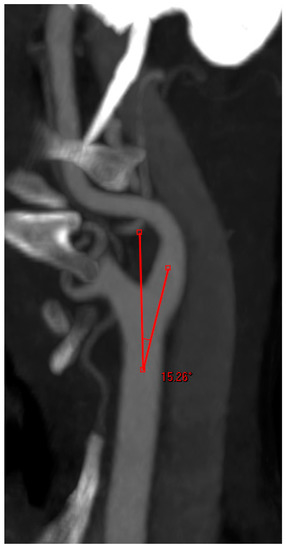

- Angle between the AA and the supra-aortic vessel: measured on the treated side only, through a multiplanar reconstruction and visualization of the AA in coronary and left anterior oblique (LAO) projection. One arm of the angle was drawn along the outer curvature of the AA and the second arm was placed in the middle of the CCA or brachiocephalic trunk. The right-side angle was chosen for selection criteria (Figure 3);

Figure 3. Angle measurement between the aortic arch and supra-aortic vessel.